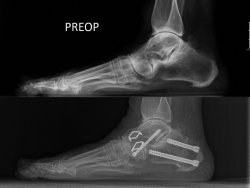

El pie plano valgo también puede ser el resultado patomecánico de una compensación de un equinismo (gastrodependiente o no). Los fenómenos “de escape” de un equinismo –pronación tarsiana y rotación externa del pie en la marcha– suelen observarse con frecuencia juntos(14).

Figura 2. La pronación tarsiana (izquierda) puede ser un mecanismo de escape frente a un equinismo constitucional, al igual que la rotación externa de los pies/piernas (derecha). La combinación de ambas características “descarga” el sistema aquíleo-calcáneo-plantar, haciendo más difícil el sufrimiento mecánico del plano sagital.